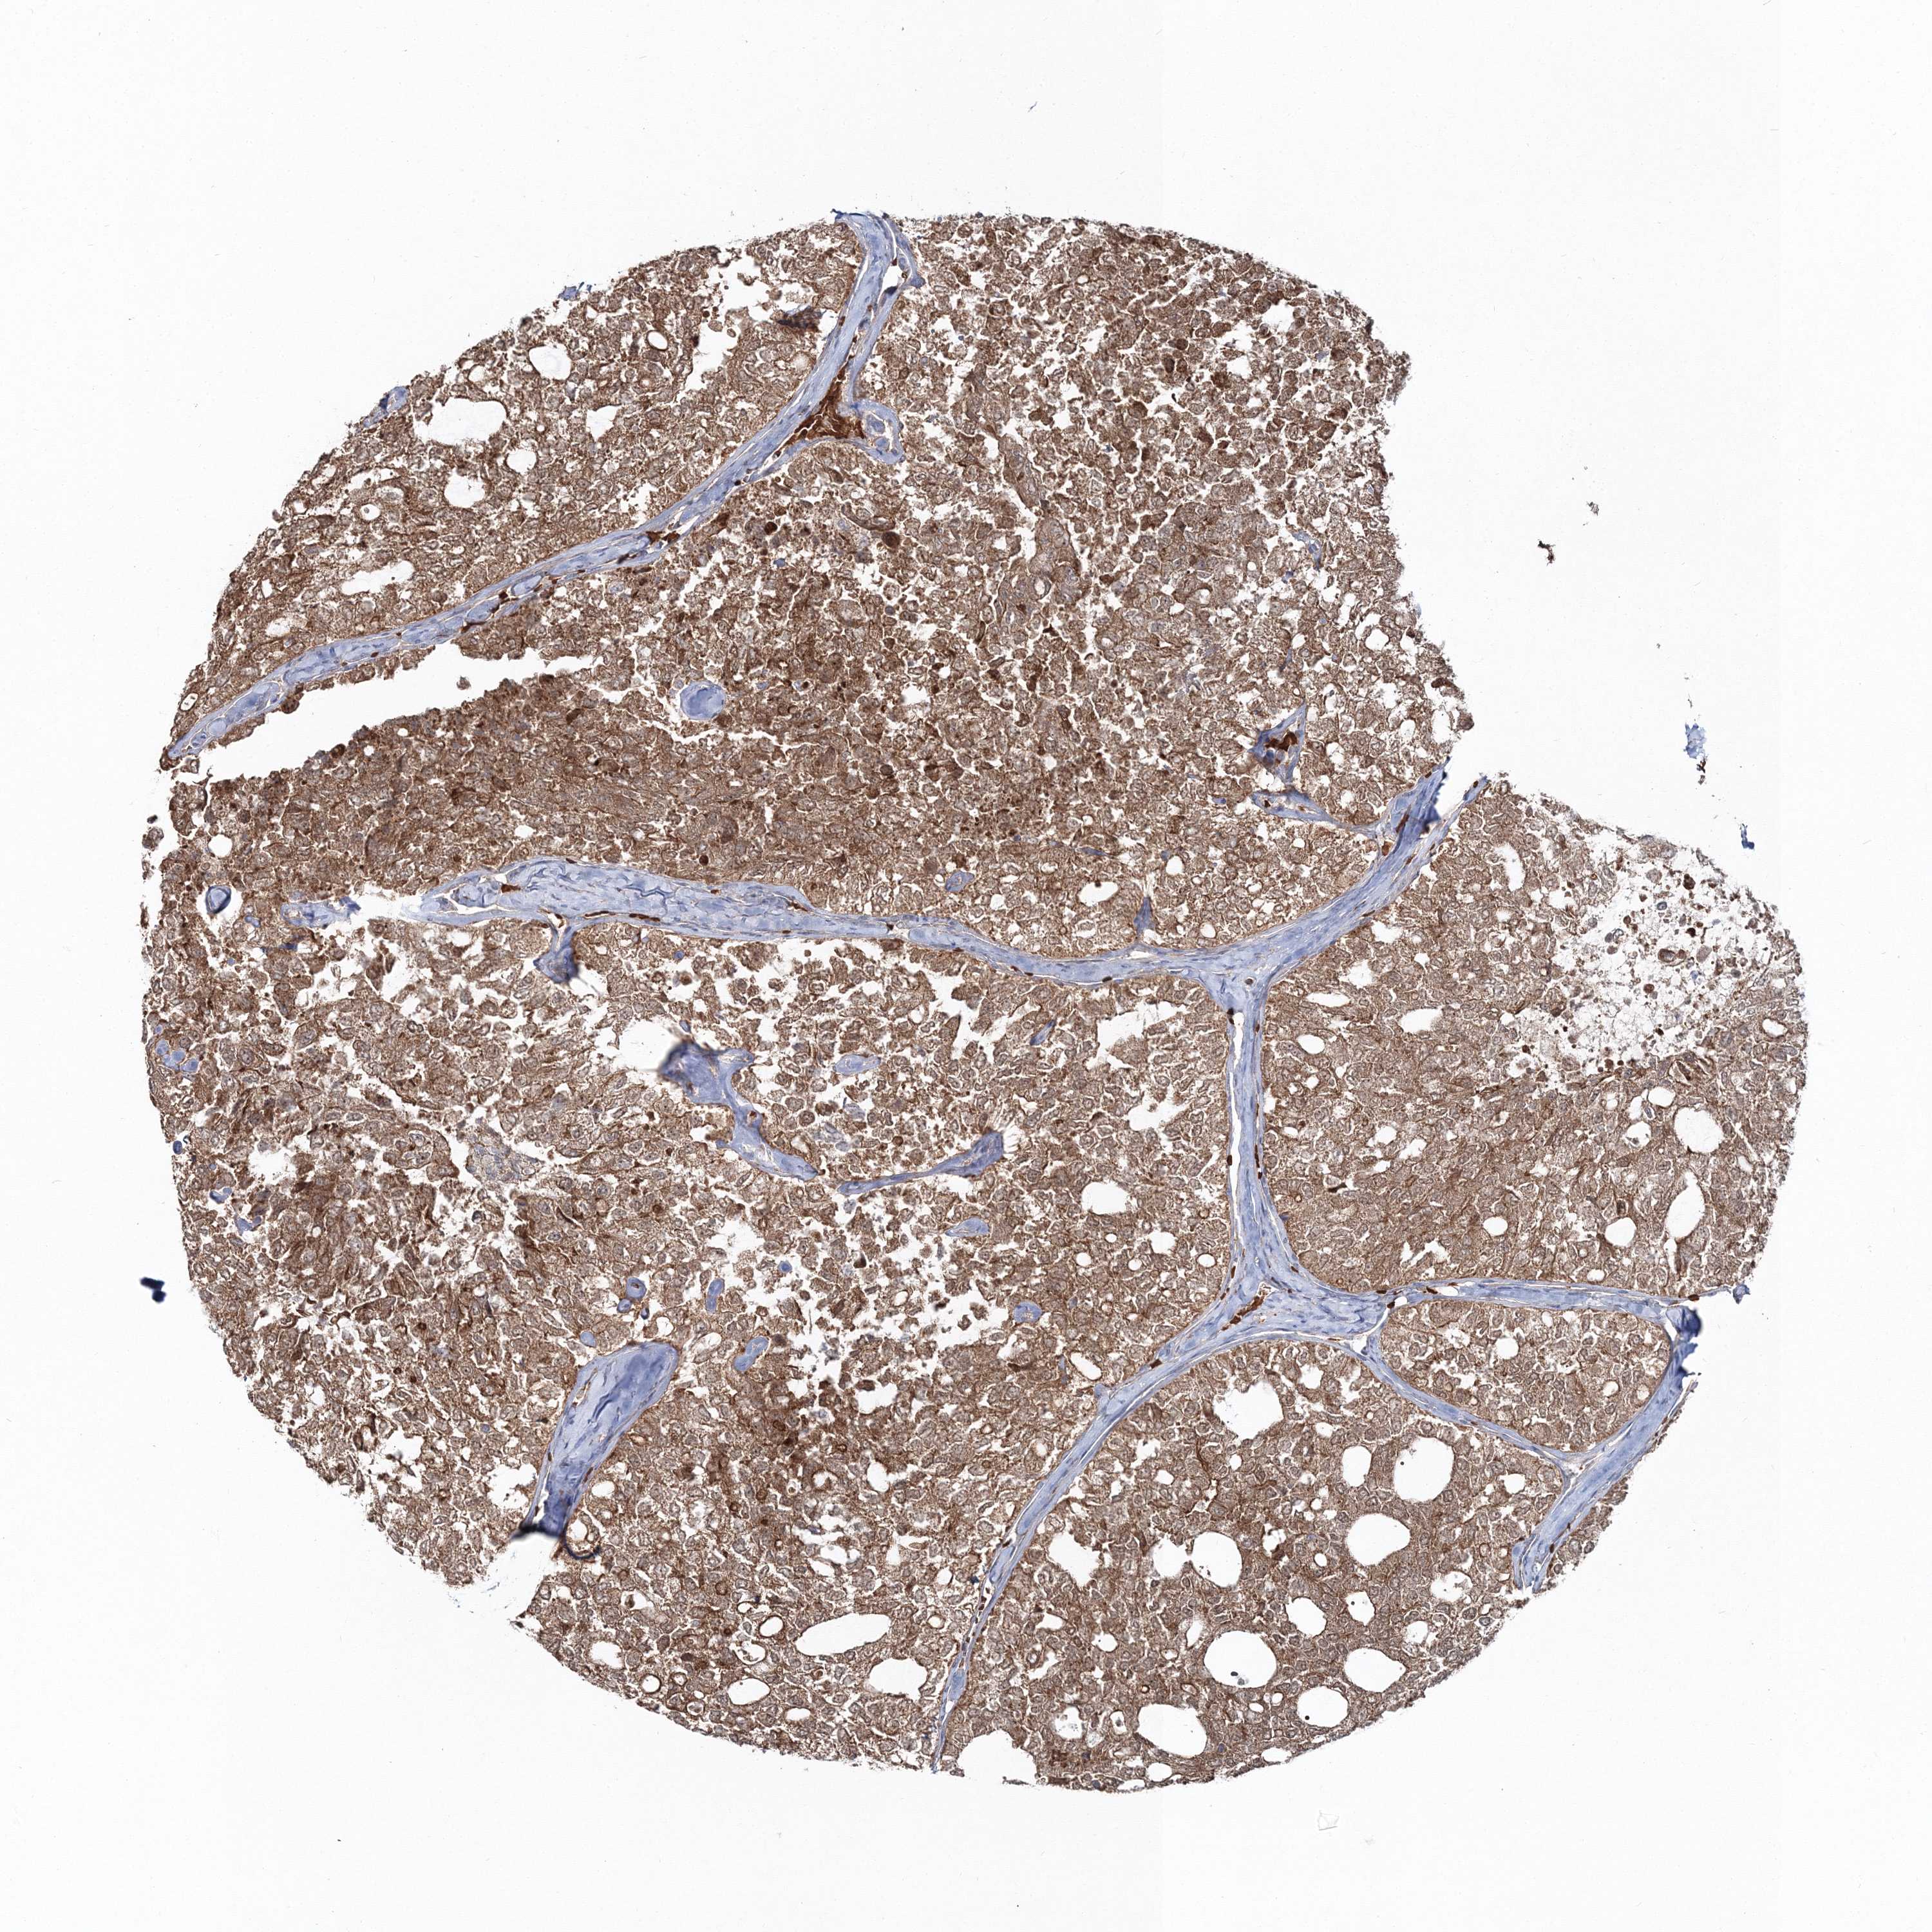

THYROID CANCER - Protein expressioni

A mouse-over function shows sample information and annotation data. Click on an image to view it in a full screen mode. Samples can be filtered based on level of antibody staining by selecting one or several of the following categories: high, medium, low and not detected. The assay and annotation is described here.

Note that samples used for immunohistochemistry by the Human Protein Atlas do not correspond to samples in the TCGA dataset.

Antibody stainingi

Antibody staining in the annotated cell types in the current human tissue is reported as not detected, low, medium, or high, based on conventional immunohistochemistry profiling in selected tissues. This score is based on the combination of the staining intensity and fraction of stained cells.

Each image is clickable and will lead to virtual microscopy that enables deeper exploration of all samples and also displays staining intensity scores, fraction scores and subcellular localization as well as patient and tissue information for each sample.

Antibody HPA036428

Staining

High

Medium

Low

Not detected

Intensity

Strong

Moderate

Weak

Negative

Quantity

>75%

75%-25%

<25%

None

Location

Nuclear

Cytoplasmic/membranous

Cytoplasmic/membranous,nuclear

Papillary adenocarcinoma, NOS

Follicular adenoma carcinoma, NOS